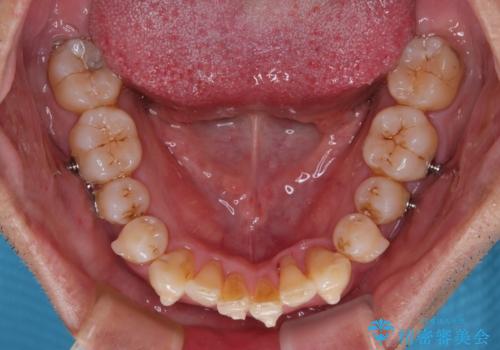

前歯のデコボコを治したい インビザラインによる矯正治療

- 前歯のデコボコを気にして来院された患者様です。

目立たない装置で手軽に治したいとのことで、インビザラインにて矯正治療を行うこととしました。

- 矯正装置

- インビザライン